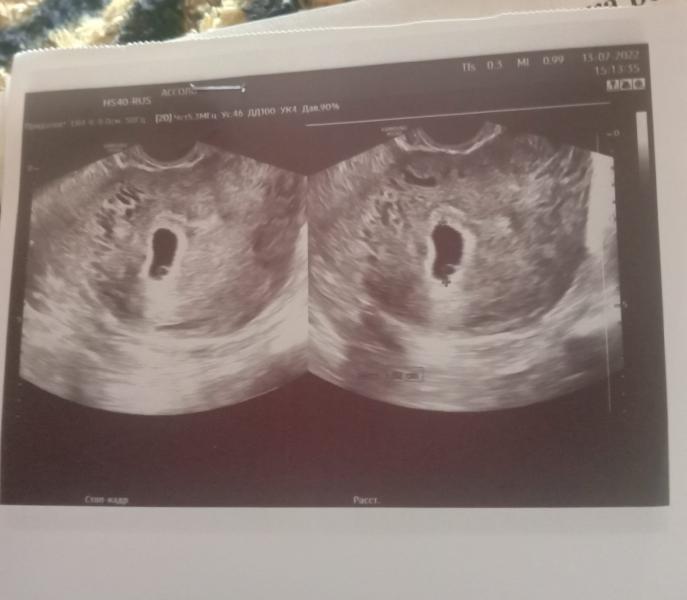

Здравствуйте девочки ну я все же не могу понять как ведеться расчет вся запуталась первый день последних месячный был 31.05.2022.ждали 2 полоски первое узи сделали 5.07.2022 поставили беременность 3 недели. Яйцо плодное 3 мм желточного мешечка небыло .Второе узи я сделала 13.07.2022 прошла неделя ставят 5 недель плодное яйцо 18мм желточный мешечек 2 мм эмбриончика еще нет. За неделю выросло в 6 раз . вот и не пойму как считают и какой у меня срок и все ли по сроку норма

@viktoriaazykova1 я Вам уже сказала, что считают они некорректно. Нет такого акушерского срока 3 недели, его на узи не видно. Второй протокол, где 5 недель акушерских написано, скорее всего, по размерам плодного яица посчитано. Но по факту у Вас уже 7 должно быть, а не 5.

По акушерскому сроку у Вас 8 недель и 2 дня, эмбрион уже должен быть и сердцебиение. Плодное яйцо растет, но пустое. Здесь два варианта, либо поздняя овуляция либо анэмбриония. УЗИ ставит тоже акушерский срок, не от зачатия. Если есть сильные разногласия, больше 2-х недель, то не исключено, что есть проблемы в развитии беременности.